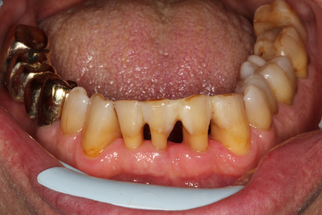

В основной группе 2 на фоне проводимого комплексного лечения с использованием геля «Метрогил-дента» отмечали улучшение как субъективных, так и объективных проявлений заболевания: уменьшались болезненность и кровоточивость десен, галитоз. Через 30 дней после лечения пациенты обеих групп отмечали значительное снижение болезненности, отека и кровоточивости десен, исчезновение неприятного запаха изо рта, некоторое снижение подвижности зубов, появление уверенности при жевании, улучшение общего состояния. При объективном обследовании отмечали уплотнение десневого края за счет уменьшения отека, существенное улучшение гигиенического состояния полости рта, прекращение выделения экссудата из пародонтальных карманов (Рисунок 13).

| до лечения | через 30 дней после лечения |

| Рисунок 13. Динамика состояния тканей пародонта у пациента с ХГП тяжелой степени через 30 дней после комплексного консервативного лечения с местным применением препарата «Метрогил-Дента» . | |